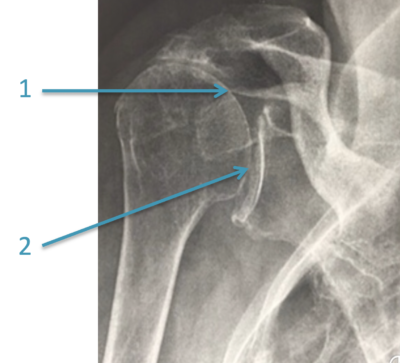

1/Diminution de l’espace entre l’acromion et la tête de l’humérus marquant la rupture de coiffe – 2/Arthrose

Quand les muscles de la coiffe des rotateurs ne fonctionnent plus. Ils n’arrivent donc plus à initier le mouvement du bras. En revanche, le muscle deltoïde est toujours valide pour le poursuivre. La prothèse inversée reposera donc sur le muscle deltoïde.

Les pathologies pouvant entrainer un problème au niveau des muscles de la coiffe sont :

• -une rupture/déchirure de coiffe des rotateurs post-traumatique non réparable,

• une arthrose de l’épaule importante,